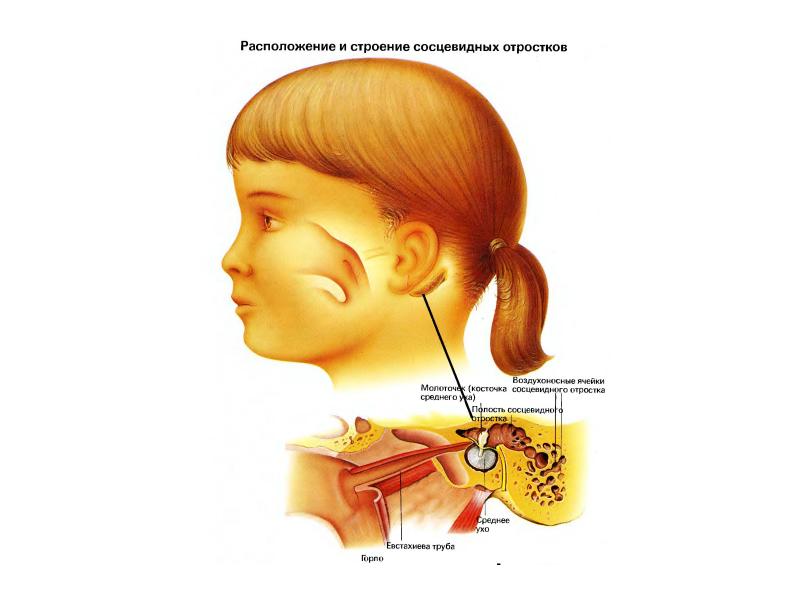

Анатомия сосцевидного отростка